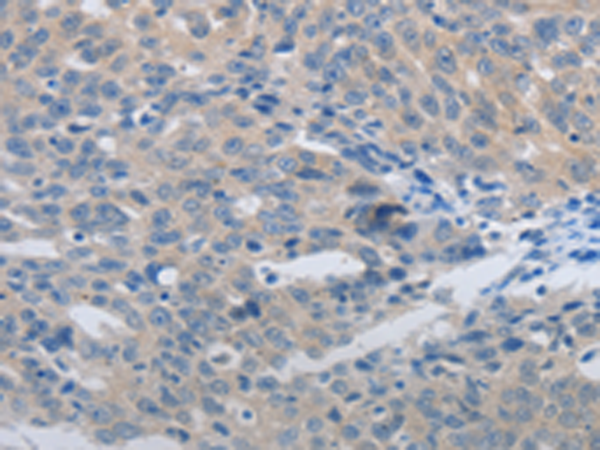

分类: 科研抗体货号: P11020别名: MCT2应用: WB,IHC反应种属: Human